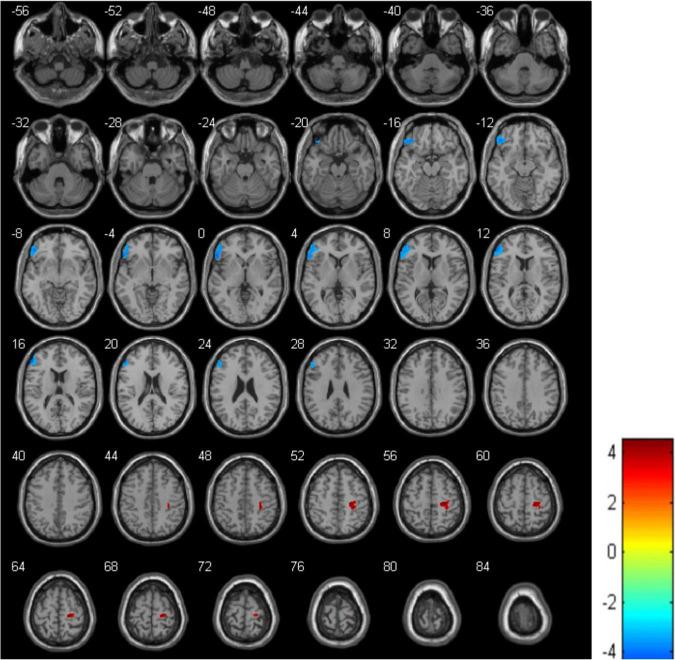

Compared with HCs, MDD patients had a lower rCBF in the left triangular part of the inferior frontal gyrus (IFGtriang) but a higher one in the right Precental gyrus (PreCG). Negative correlations were also noted between the CBF in the left IFGtriang and the Hamilton depression scale (HAMD) scores of MDD patients.

结果

与HCs相比,MDD患者左下额回三角部(IFGtriang)的rCBF较低,但右中央前回(PreCG)的rCBF较高。还发现MDD患者左IFGtriang的CBF与汉密尔顿抑郁量表(HAMD)得分之间呈负相关。